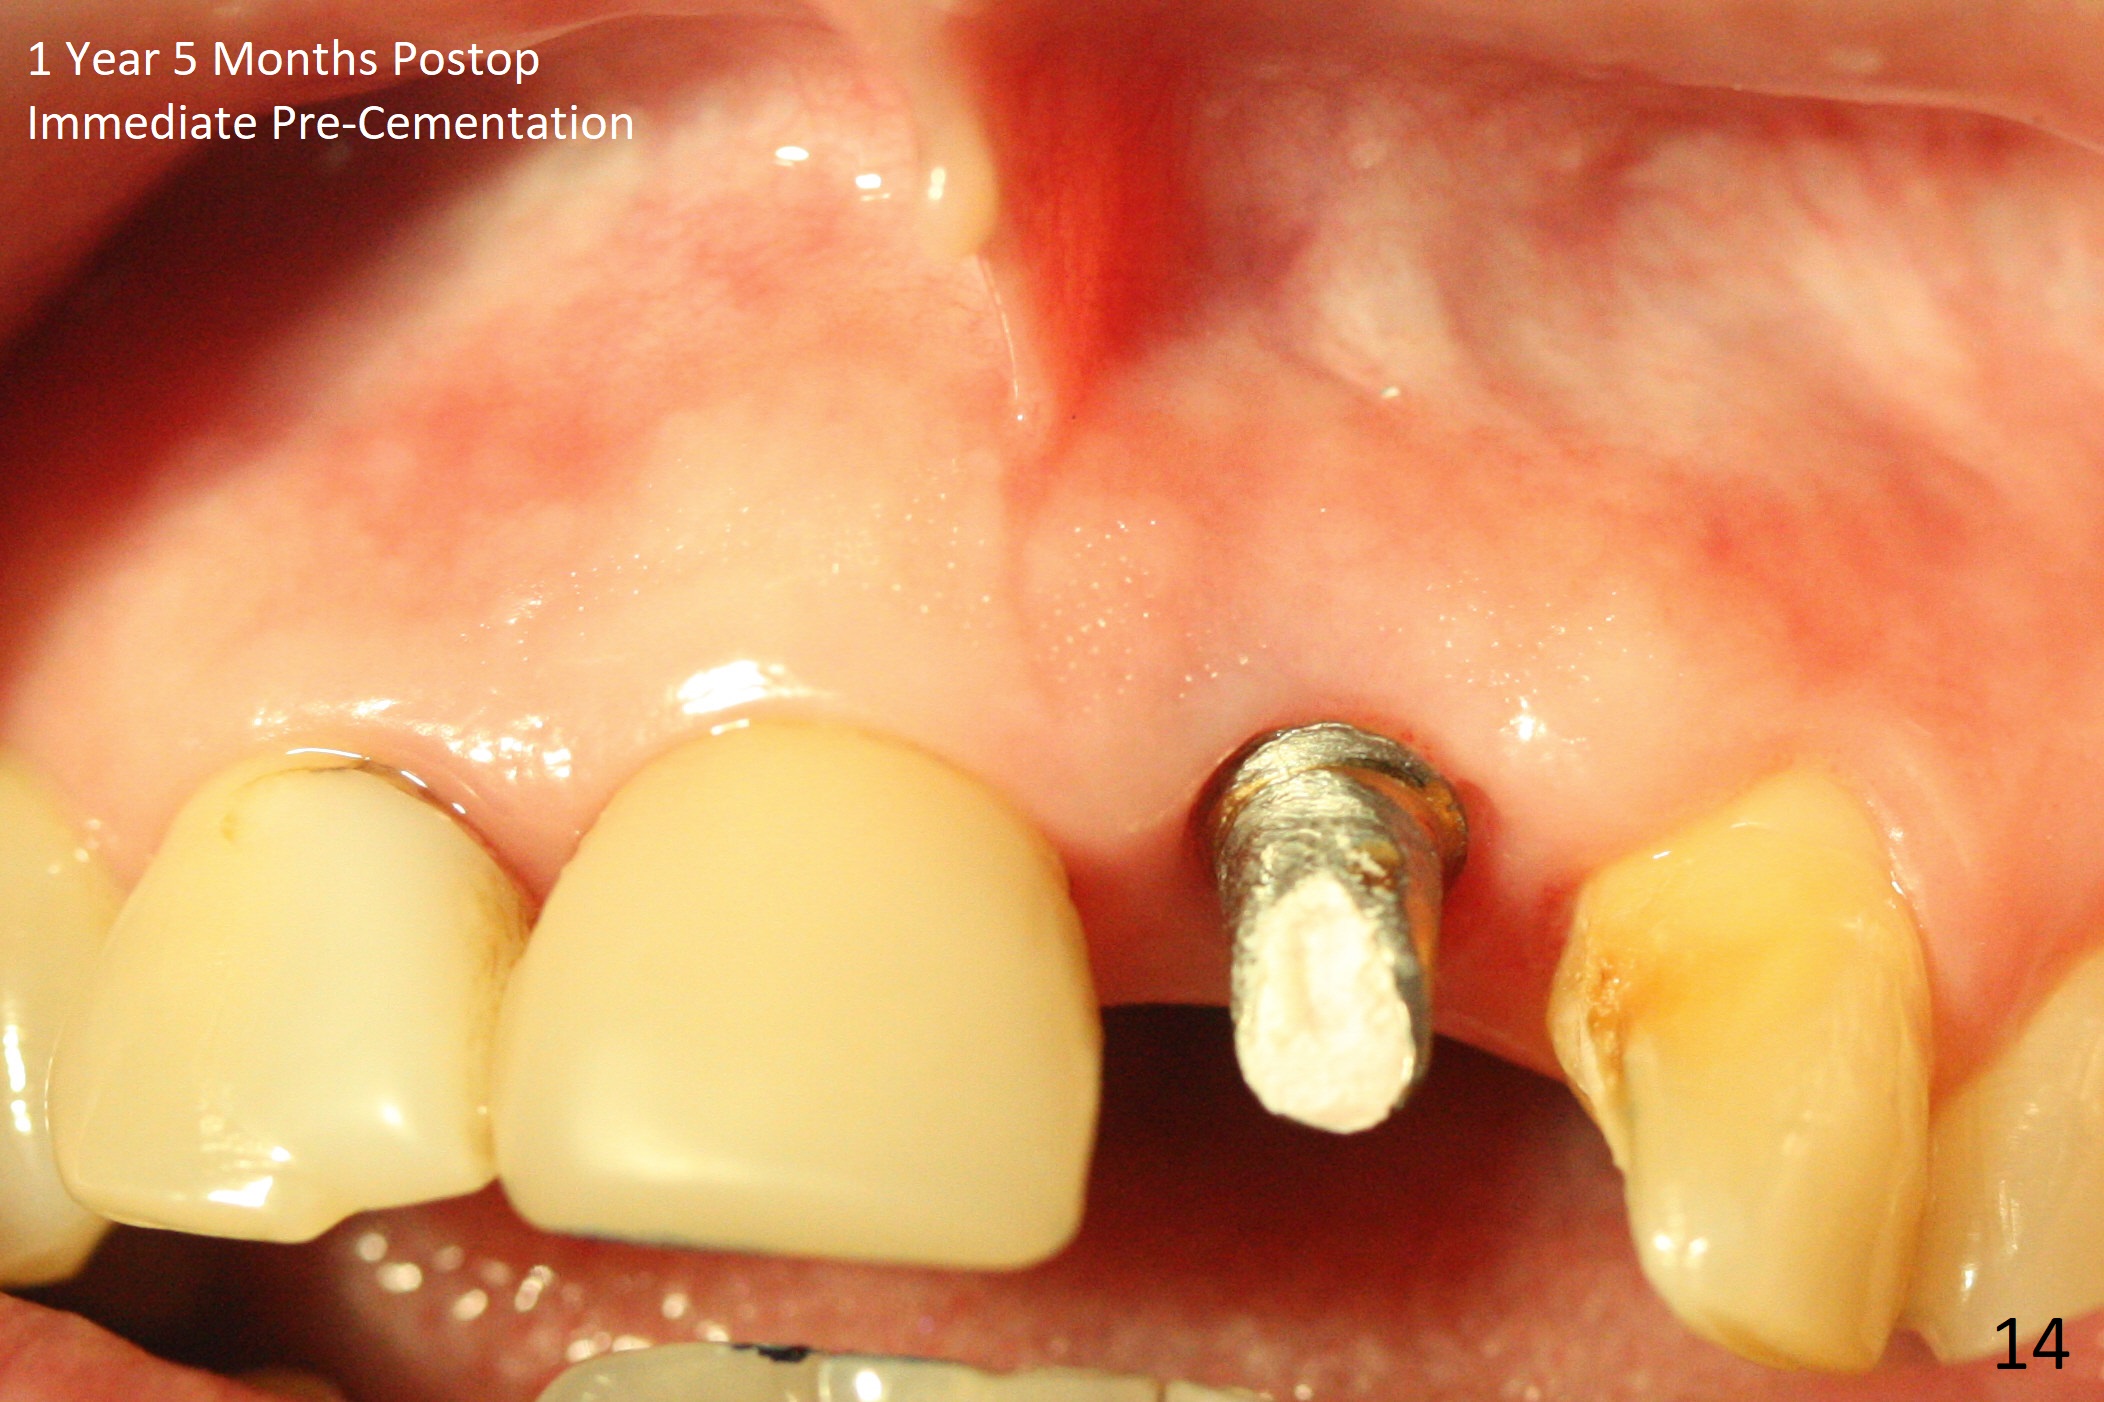

In spite of the incisobuccal shift of the tooth #9 with gingival recession (Fig.1) and loss of the buccal plate (intraop finding), there is no buccal contour collapse (Fig.2 *), due to the presence of the buccal bone of the neighboring teeth and the root of the affected tooth. After extraction, osteotomy (Fig.3) and dummy implant try in (Fig.4), a definitive implant is placed palatally with the buccal gap (Fig.5 *). In fact there is mild buccal contour collapse prior to bone graft (Fig.5 arrow). When allograft (Vera, Fig.6,7 *) is packed buccal to the implant and overlying abutment as a solid support, the buccal contour seemingly returns normal (Fig.6 arrowhead). An immediate provisional is fabricated to prevent loss of the bone graft during healing period. Bone graft kept in place by the provisional turns yellow 6 days postop (Fig.8). The buccal plate remains strong, while the fistula becomes indistinguishable. After adjustment of the provisional margin a few times (nearly 3 months postop, Fig.9,10), the gingival margin appears to have grown incisally, as compared to Fig.1. There is minimal buccal bone collapse (Fig.10). Dislodgement of the abutment and provisional forces her to return 1 year 4 months postop; the socket has healed (Fig.11). The buccal plate is not concave 1 year 4 months postop (Fig.12). The gingiva is slightly recessive (Fig.13) with mild buccal plate concavity (Fig.14) immediately before cementation. The implant could be placed ~ 1 mm deeper (Fig.15).